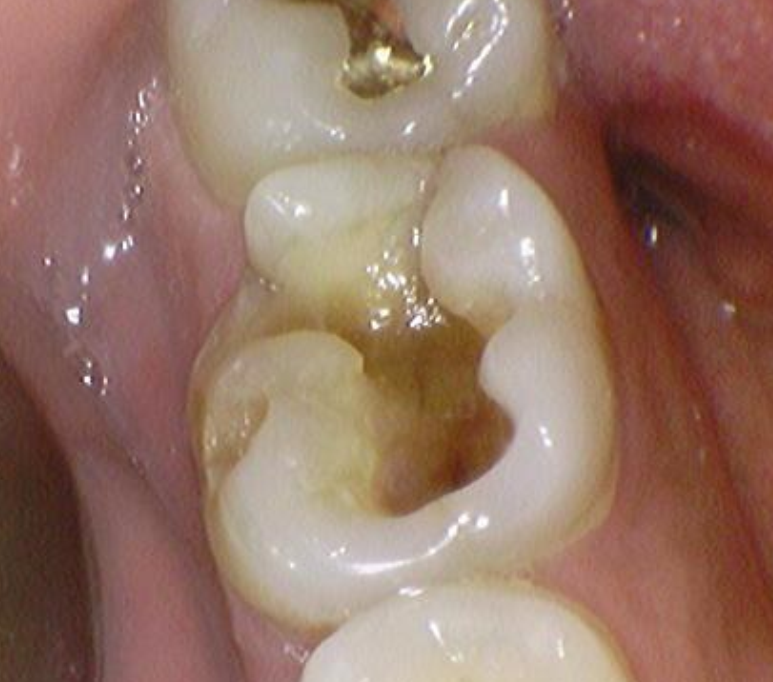

23.05.06(육안상 발견된 균열선)

금인레이 재료가 수복되어 있을 때에도 시큰시큰 불편한 느낌이 있었으며 특히 음식물을 씹을 때 심한 시큰거림으로 치과 내원을 고민하셨다고 하셨습니다.

금재료가 탈락되면서 시리고 시큰거리는 증상은 더 심해졌고 최근에는 물만 닿아도 굉장히 아픈 느낌이 들었다고 이야기 해주셨습니다.

다행히 엑스레이 소견 상 치아의 신경을 침범하지는 않았고, 치아의 균열선만 육안으로 관찰되는 상태였습니다.